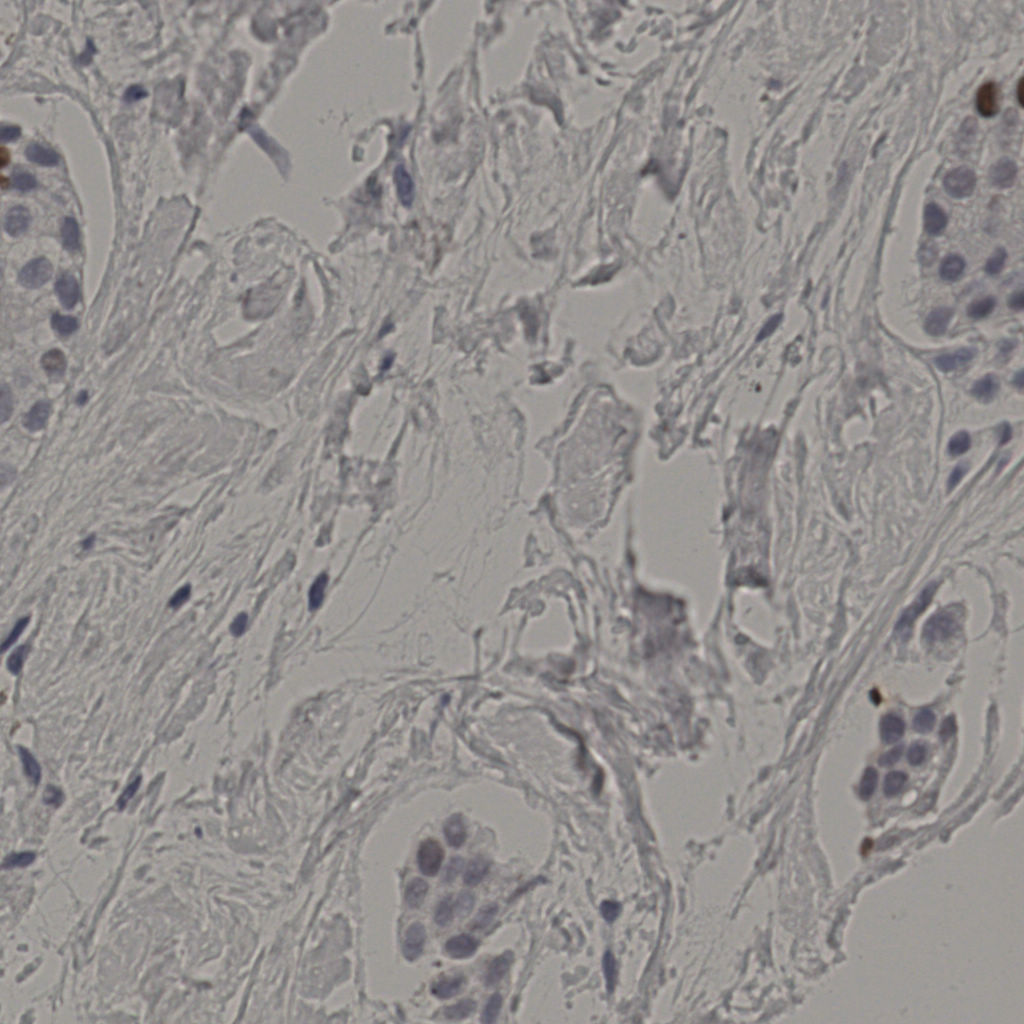

5.31%

Ki67 指数

阴 19502

阳 1093

切片统计

总切片

2970

有效

554

已标记

有效率

19%

标记后

标记前